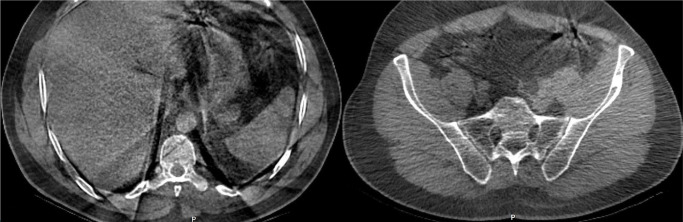

Intraosseous lipomas (IOLs) are rare benign bone tumors which can closely mimic malignancy on imaging, leading to diagnostic challenges. A 34-year-old male patient was admitted with persistent knee pain which was initially suspected to be metastatic bone disease. The patient reported activity-related pain relieved by rest. Physical examination revealed mild tenderness without swelling or restricted motion. Laboratory findings, including serum calcium and inflammatory markers, were normal. Magnetic resonance imaging (MRI) showed hyperintense lesions in the tibial and femoral metaphyses with surrounding bone marrow edema, raising suspicion of malignancy. Bone scintigraphy revealed increased radionuclide uptake in the tibial tuberosity, iliac crest, and the ninth rib, further mimicking metastatic disease. A biopsy of the tibial lesion confirmed mature adipocytes without necrosis or atypia, diagnosing IOLs. The patient was managed conservatively with non-steroidal anti-inflammatory drugs and physiotherapy. At three months, symptoms resolved completely, with no recurrence or new complaints. Follow-up MRI confirmed lesion stability. In conclusion, this case highlights the diagnostic complexity of IOLs and emphasizes the need for multimodal imaging and histopathological confirmation to differentiate benign lesions from malignancies. Including IOLs in the differential diagnosis of unexplained bone pain can prevent unnecessary invasive procedures and mistreatment.